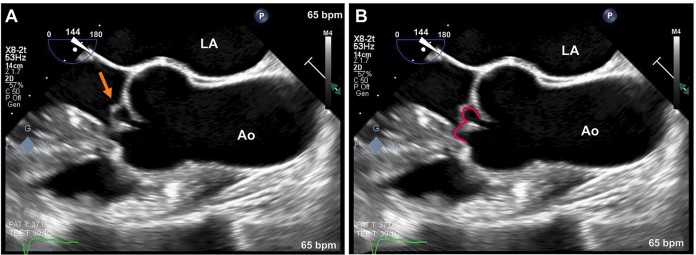

Ecocardiograma transesofágico, realizado para confirmar o mecanismo da regurgitação aórtica, mostrou uma valva aórtica trivalvular com uma dobra transversa no folheto coronariano direito causando prolapso distal.

O sinal em “W” pode ser observado, ao estudo transesofágico no eixo longo, com a análise em 3D caracterizando a dobra transversa. Este sinal se caracteriza por um formato em W do segmento prolapsado do folheto coronariano direito.